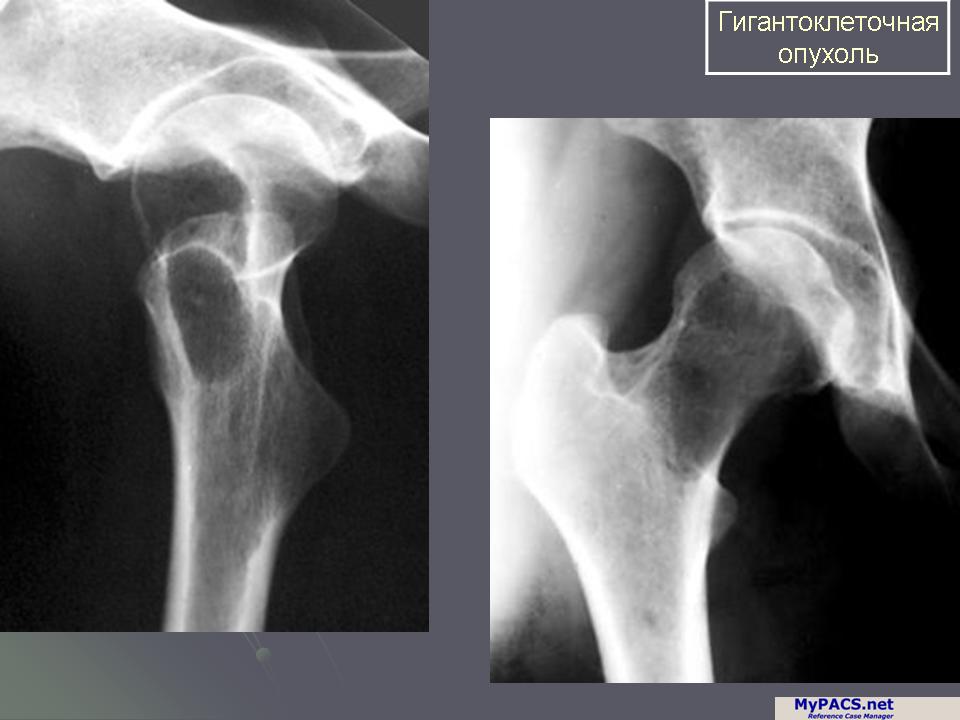

Рентгеновские снимки доброкачественных опухолей костей